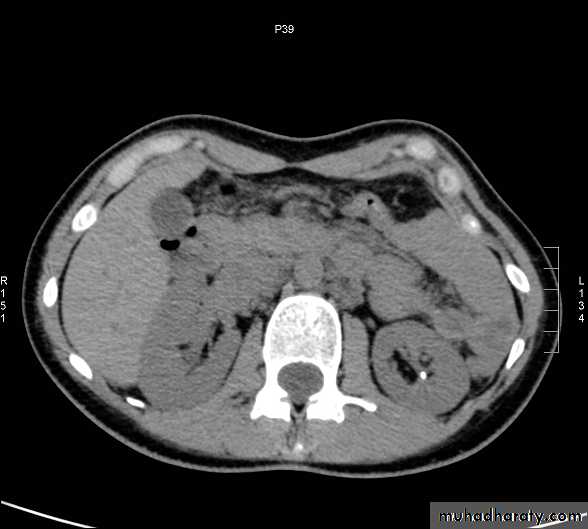

CT scanContrast enhanced CT scan through the kidneys in nephrogram phase 90-100 seconds following contrast administration and would show renal lesions well.